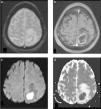

Abscesos cerebrales bacterianos inespecíficos. Pacientes con AC (a y d) bacteriano cerebeloso, (b y e) encefálico subcortical y (e y f) múltiples de distribución bilateral superficial y profunda. Se ilustra el comportamiento característico de estas lesiones con el realce anular clásico en (a, b y c) las secuencias ponderadas en T1 con contraste y (d, e y f) el intenso fenómeno de restricción en el centro necrótico en la difusión, típico de estas lesiones.

En las etapas precoces del proceso infeccioso bacteriano, cerebritis y fase de encapsulación primaria, la restricción no es tan marcada, por lo que existen dificultades al momento de realizar el diagnóstico diferencial15,18.

En la práctica, la distinción entre los tipos de AC únicamente con secuencias convencionales es muy compleja. Si utilizamos la DWI, sumado a un análisis minucioso de la morfología de las lesiones, el contexto clínico y el estado de inmunidad del paciente, se puede arribar al diagnóstico de forma más precisa.